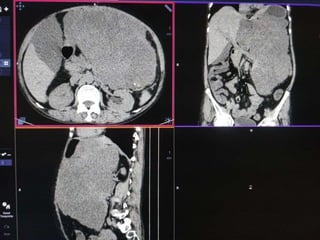

CASE2

DIFFERENTIALS

Diagnosis Points in favour Points against

Retroperitoneal

sarcomas

• Leiomyosarcoma

/Undifferentiated

Liposarcoma

• MFH

Age and clinical

presentation

Imaging features

(Large ill defined

heterogeneously

enhancing lesion

with areas of

necrosis)

No fat density/

calcification

No calcification

GIST Age

Biopsy:

 Poorly differentiated Leiomyosarcoma